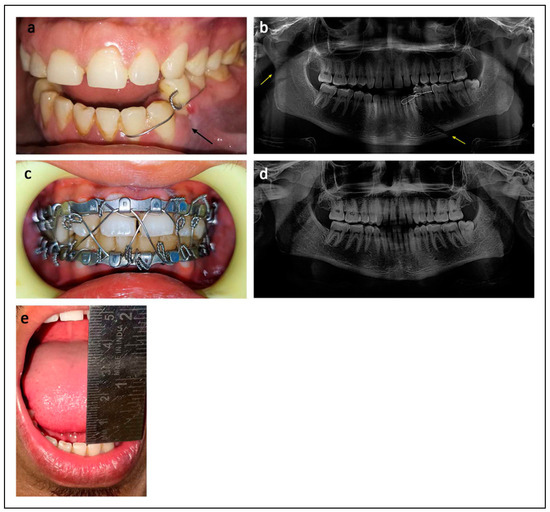

- Blitz, M.; Notarnicola, K. Closed reduction of the mandibular fracture. Atlas Oral Maxillofac. Surg. Clin. 2009, 17, 1–13. [Google Scholar] [CrossRef] [PubMed]

- Omeje, K.U.; Rana, M.; Adebola, A.R.; et al. Quality of life in treatment of mandibular fractures using closed reduction and maxillomandibular fixation in comparison with open reduction and internal fixation—A randomized prospective study. J. Craniomaxillofac. Surg. 2014, 42, 1821–1826. [Google Scholar] [CrossRef] [PubMed]

- Osunde, O.; Omeje, K.; Efunkoya, A.; Adebola, A. Oral health-related quality of life in non-surgical treatment of mandibular fractures: A pilot study. Niger. J. Exp. Clin. Biosci. 2015, 3, 8–13. [Google Scholar] [CrossRef]